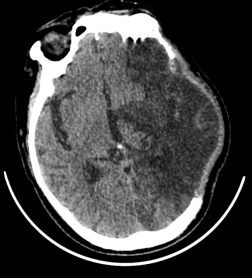

图片

出院前颅脑CT

在医护人员和家属的精心照顾下,“奇迹”终于发生了。

病人颅内水肿逐渐消退,精神状态好转,开始对声音、光线等刺激产生反应并逐渐灵敏,醒来后可以清晰地分辨出家人并叫出他们的名字,一家人喜极而泣!现在病人能自己吃饭、说话,可以与他人交流,四肢也可以活动了,可在一人帮助下下床行走各项指标恢复正常,贫血、营养不良、肺部感染、睡眠紊乱显著改善,逐步拔除胃管、气管套管、尿管。